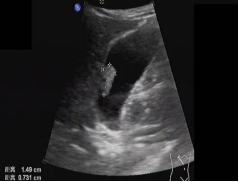

首选检查为超声检查,该检查无创、方便易行、廉价,对息肉的形态、血流有很好的判断,尤其对胆囊胆固醇沉积症、胆囊腺肌症等有独特的影像显示,是常规体检、随访的必备检查。

超声检查未探及血流信号,密切随访,每半年至一年进行一次超声检查。

如超声检查探及血流信号,则肿瘤性息肉可能性大,不论息肉大小,应及时行胆囊切除术。